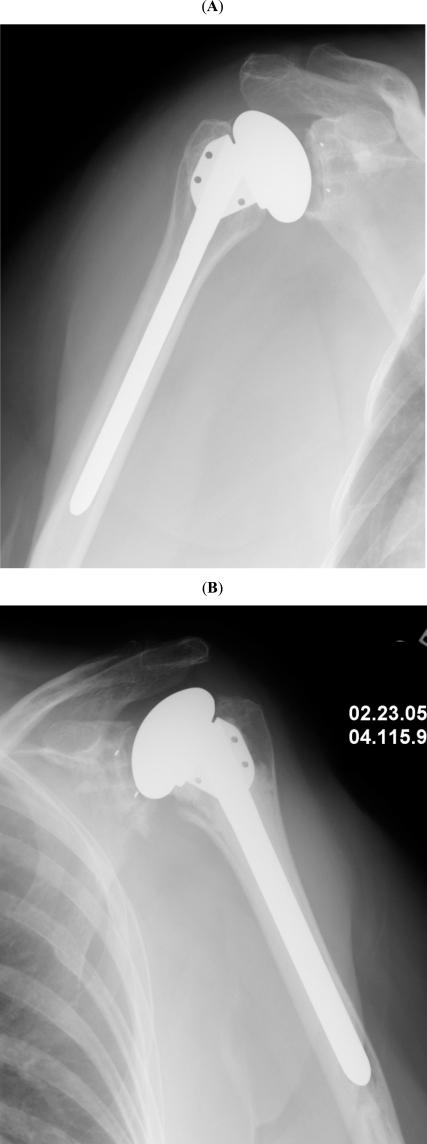

Total shoulder arthroplasty.

Shoulder arthroplasty has been the subject of marked advances over the last few years. Modern implants provide a wide range of options, including resurfacing of the humeral head, anatomic hemiarthroplasty, total shoulder arthroplasty, reverse shoulder arthroplasty and trauma-specific implants for fractures and nonunions. Most humeral components achieve successful long-term fixation without bone cement. Cemented all-polyethylene glenoid components remain the standard for anatomic total shoulder arthroplasty. The results of shoulder arthroplasty vary depending on the underlying diagnosis, the condition of the soft-tissues, and the type of reconstruction. Total shoulder arthroplasty seems to provide the best outcome for patients with osteoarthritis and inflammatory arthropathy. The outcome of hemiarthroplasty for proximal humerus fractures is somewhat unpredictable, though it seems to have improved with the use of fracture-specific designs, more attention to tuberosity repair, and the selective use of reverse arthroplasty, as well as a shift in indications towards internal fixation. Reverse shoulder arthroplasty has become extremely popular for patients with cuff-tear arthropathy, and its indications have been expanded to the field of revision surgery. Overall, shoulder arthroplasty is a very successful procedure with predictable pain relief and substantial improvements in motion and function.